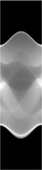

The Radon transform data is often called a sinogram because the Radon transform of an off-center point source is a sinusoid. Consequently the Radon transform of a number of small objects appears graphically as a number of blurred sine waves with different amplitudes and phases.